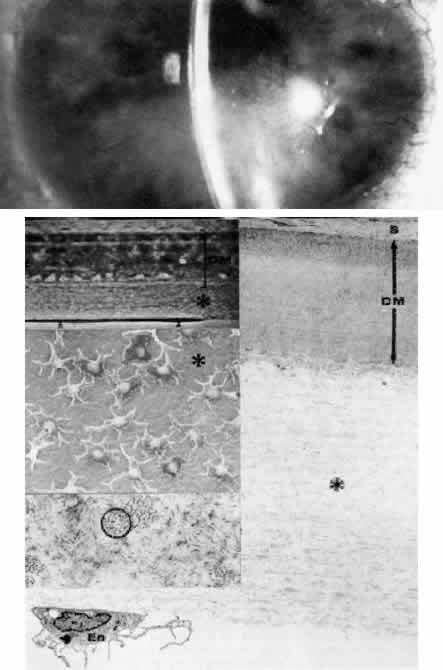

Central Crystalline Dystrophy (Schnyder)

This dominantly inherited dystrophy occurs in early life and is occasionally congenital (Figs. 5 AND 12).145–147 The main feature of the disease is a bilateral, axial, ring-shaped corneal opacity consisting of polychromatic crystals (Color Plate 1 I) .

Fig. 12. Central crystalline dystrophy (Schnyder). Top left. Clinical appearance of eye of 20-year-old woman includes ovoid crystalline deposit with clear surrounding stroma and without arcus lipidis. Visual acuity is 20/40. Bottom left. Light microscopy of cornea demonstrates epithelial irregularity and numerous crystalline profiles (circled) in Bowman's layer and stroma (toluidine blue, × 350). Right. Transmission electron micrograph demonstrates basal epithelium (E) with thickened basement membrane complexes (arrowhead), disorganized Bowman's layer (B), and polygonal crystalline profiles (*) typical of cholesterol. The keratocyte (K) is unremarkable (× 10,400). (Gipson I: Schnyder's crystalline dystrophy. Trans Am Ophthalmol Soc 76: 184, 1978)

The yellow-white opacity is noted in Bowman's layer and the anterior stroma. The epithelium is normal, and the uninvolved stroma also appears normal, although in time a diffuse stromal haze can develop. In some cases, small white opacities scattered throughout the stroma have been noted.148 Histologic examination using lipid stains on frozen sections reveals neutral fats and cholesterol.149 The clinically apparent crystals correspond to cholesterol accumulations, both within keratocytes and extracellularly. Neutral fat is distributed within the stroma among the collagen fibrils. Both the limbal girdle of Vogt and corneal arcus are associated with this dystrophy. The disease may be considered a localized defect of lipid metabolism, although some patients may also exhibit hypercholesterolemia, xanthelasma, and genu valgum. Because the disorder stabilizes with time, only occasional patients with severe opacity require corneal grafting.

It is important to perform cholesterol and lipid studies on these patients since, although the severity of a systemic lipid abnormality does not necessarily correlate with the severity of the corneal disease, elevated serum lipid levels and concomitant cardiovascular disease are associated features in some patients.150